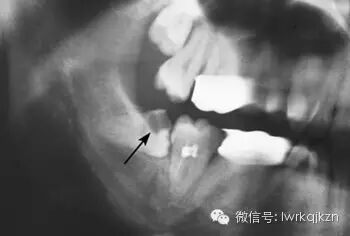

二、影响邻牙:如果生长空间不足,智齿会使劲儿顶住相邻的牙齿继续生长,可能导致邻牙损伤最后两颗牙齿都保不住。

得了智齿,忍忍就过了,你这样想可就错了,如果智齿不加以重视,可能就是这看似不起眼的小麻烦,让你痛苦万分,智齿的最大危害就是极其容易造成食物嵌塞,由于智齿不能完整地萌出在正常位置,因此与前面的牙齿不能形成良好的接触关系,那么就容易有食物残渣、细菌等滞留于智齿与其前面相邻牙齿之间的间隙中,这样容易造成智齿前面邻牙的龋坏,然后可能发展为牙髓炎。